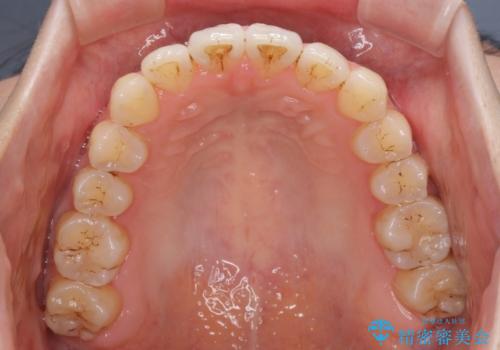

オープンバイトのインビザラインを用いた再矯正

- 矯正治療の後戻りを気にして来院された患者様です。

オープンバイト(前歯の開咬)と下顎骨の偏位による不正咬合が認められました。

骨格の偏位による不正咬合は改善しきれないことを理解いただいた上で、インビザラインにて矯正治療を行うこととしました。

オープンバイトは後戻りを起こしやすいため、極力そのリスクを軽減するため、奥歯を圧下させるように治療を進めていきました。

下顎骨の偏位が顕著であったため、上下の正中を合わせることはできませんでしたが、患者様には大変満足していただきました。